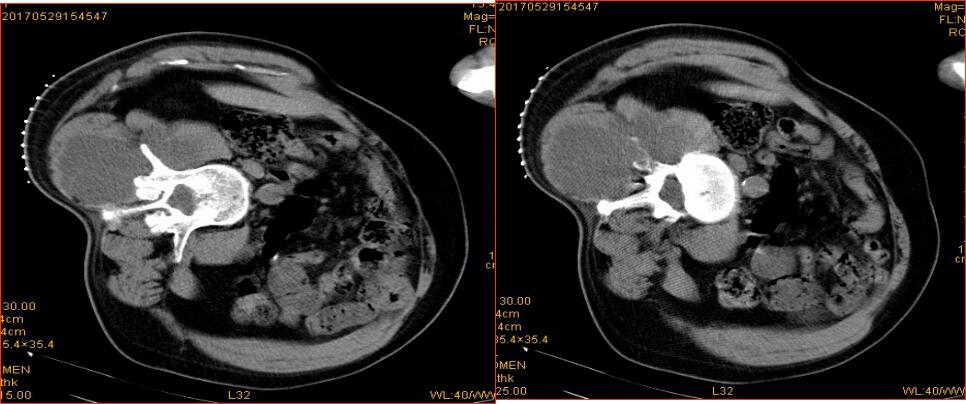

氩氦刀冷冻前定位